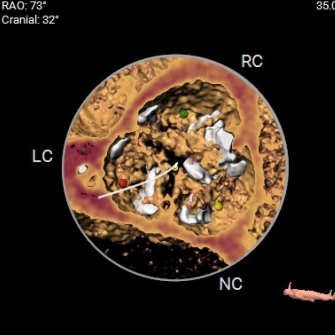

三叶瓣,瓣环大小适中,无冠窦钙化较重,窦部空间合适,左冠开口高度低,双下肢入路可。

综合各项评估,手术团队采取右侧为主入路,鉴于左冠风险,决定先用10mm球囊,再用22mm球囊预扩,植入Evolut PRO 29mm瓣膜、Cusp Overlap标准6步植入法、20Fr导引鞘。